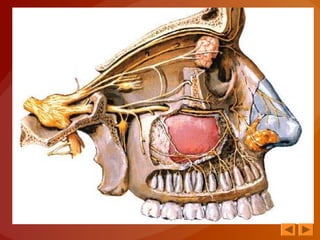

• Es un nervio sensitivo

• ORIGEN REAL

Células nerviosas situadas en la mucosa

olfatoria, que cubre la porción superior de

las paredes externa e interna de las fosas

nasales, desde la lámina cribosa del

etmoides hasta el borde inferior del cornete

superior

• ORIGEN APARENTE

Cara inferior del bulbo olfatorio

• Los filetes del nervio olfatorio discurren

por debajo de la mucosa olfatoria y llegan

convergiendo a la lámina cribosa del

etmoides

TRAYECTO